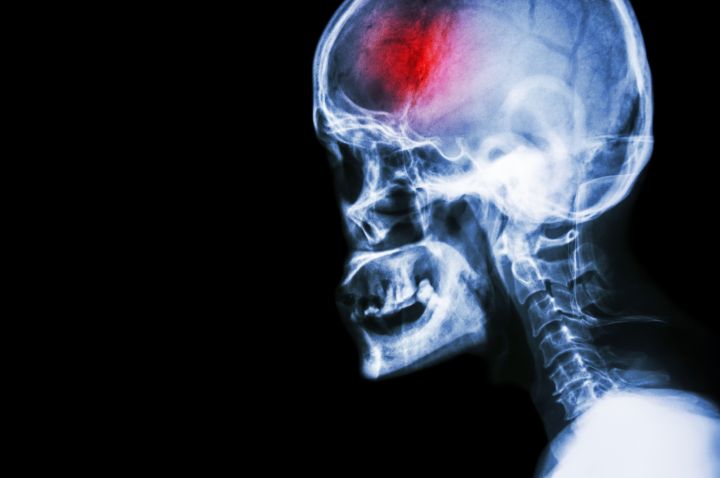

World-first research led by La Trobe University has found that injecting human amniotic cells discarded after birth into stroke patients can significantly reduce brain injury and aid recovery.

The seven-year research project led by La Trobe’s Professor Chris Sobey and with researchers from Monash University and Monash Health found that when human amnion epithelial cells – the cells lining the human amniotic sac during pregnancy and discarded after birth – were injected after stroke, impact was less severe and recovery was significantly improved.

“If we administered human amnion epithelial cells 90 minutes after stroke, the cells quickly homed in on the affected area of the brain, greatly reducing inflammation and nerve cell death,” Professor Sobey said.